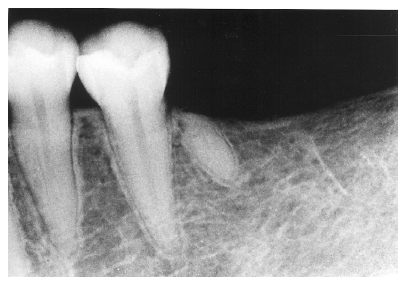

Figure 15 - Lateral Radicular Cyst

Figure 15

If the process starts from a lateral, rather than an apical canal, a lateral radicular cyst can occur. Notice how the cystic formation in Figure 15 follows the lateral aspect of the tooth root, thus differentiating it from an apical cyst.